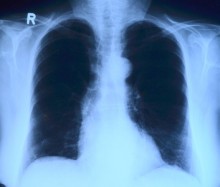

«В рамках реализации Госпрограммы «Саламатты Қазақстан» мы достигли значительных успехов в снижении заболеваемости и смертности населения от туберкулеза, заболеваемость туберкулезом в стране за 6 лет снизилась в 1,6 раза, смертность - в 2,6 раза», - подчеркнул Алексей Цой.

Вице-министр также отметил, что по разным экспертным оценкам Казахстан ежегодно принимает от 300-500 тыс. до 1 млн трудовых мигрантов, из них 15% страдают инфекционным заболеваниями, в том числе туберкулезом и ВИЧ. На родину депортируются не более 1 из каждых 10 выявленных. Остальные мигранты тяжким бременем ложатся на систему здравоохранения страны. Примерно одна треть потока мигрантов приходится на два крупных города: Алматы и Астану.

В соответствии с Минимальным пакетом для трансграничного контроля и лечения туберкулеза в Европейском регионе ВОЗ (Консенсусное заявление в Вольфхезе, 2012г.) в республике принимаются меры по оказанию противотуберкулезной помощи мигрантам, больным туберкулезом. Это - расширение доступа и улучшение качества диагностики и лечения туберкулеза и туберкулеза с множественной и широкой лекарственной устойчивостью среди мигрантов. Данная работа проводится совместно с международной неправительственной гуманитарной организацией «Project HOPE» (Проект ХОУП), занимающейся проведением образовательных и благотворительных мероприятий в области здравоохранения, в рамках гранта Глобального фонда по борьбе со СПИДом, туберкулезом и малярией.

В Казахстане реализуется Комплексный план по борьбе с туберкулезом на 2014-2020 годы. Он включает мероприятия, направленные на улучшение услуг по профилактике и лечению туберкулеза среди мигрантов и инициирование регионального диалога путем проведения встреч высокого уровня. Программа, реализуемая «Project HOPE» в партнерстве с ВОЗ, Международной организацией по миграции и Международной федерацией обществ Красного Креста и Красного Полумесяца, реализуется в 7 регионах страны с самой высокой концентрацией трудовых мигрантов.